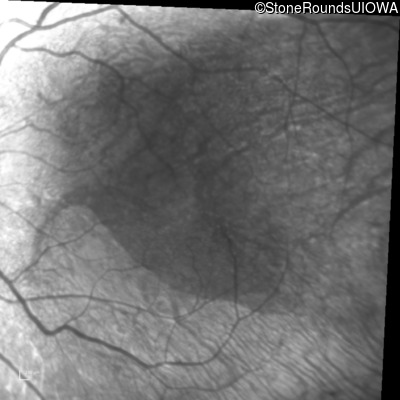

This 30 year old woman has had poor vision in her right eye for her entire life and first noticed decreased vision in dim light and constricted fields in her left eye in middle school. She had surgery in infancy for "short gut syndrome" and had liver transplantation at age 3. She also has a history of pulmonary stenosis, scoliosis, and ataxia.